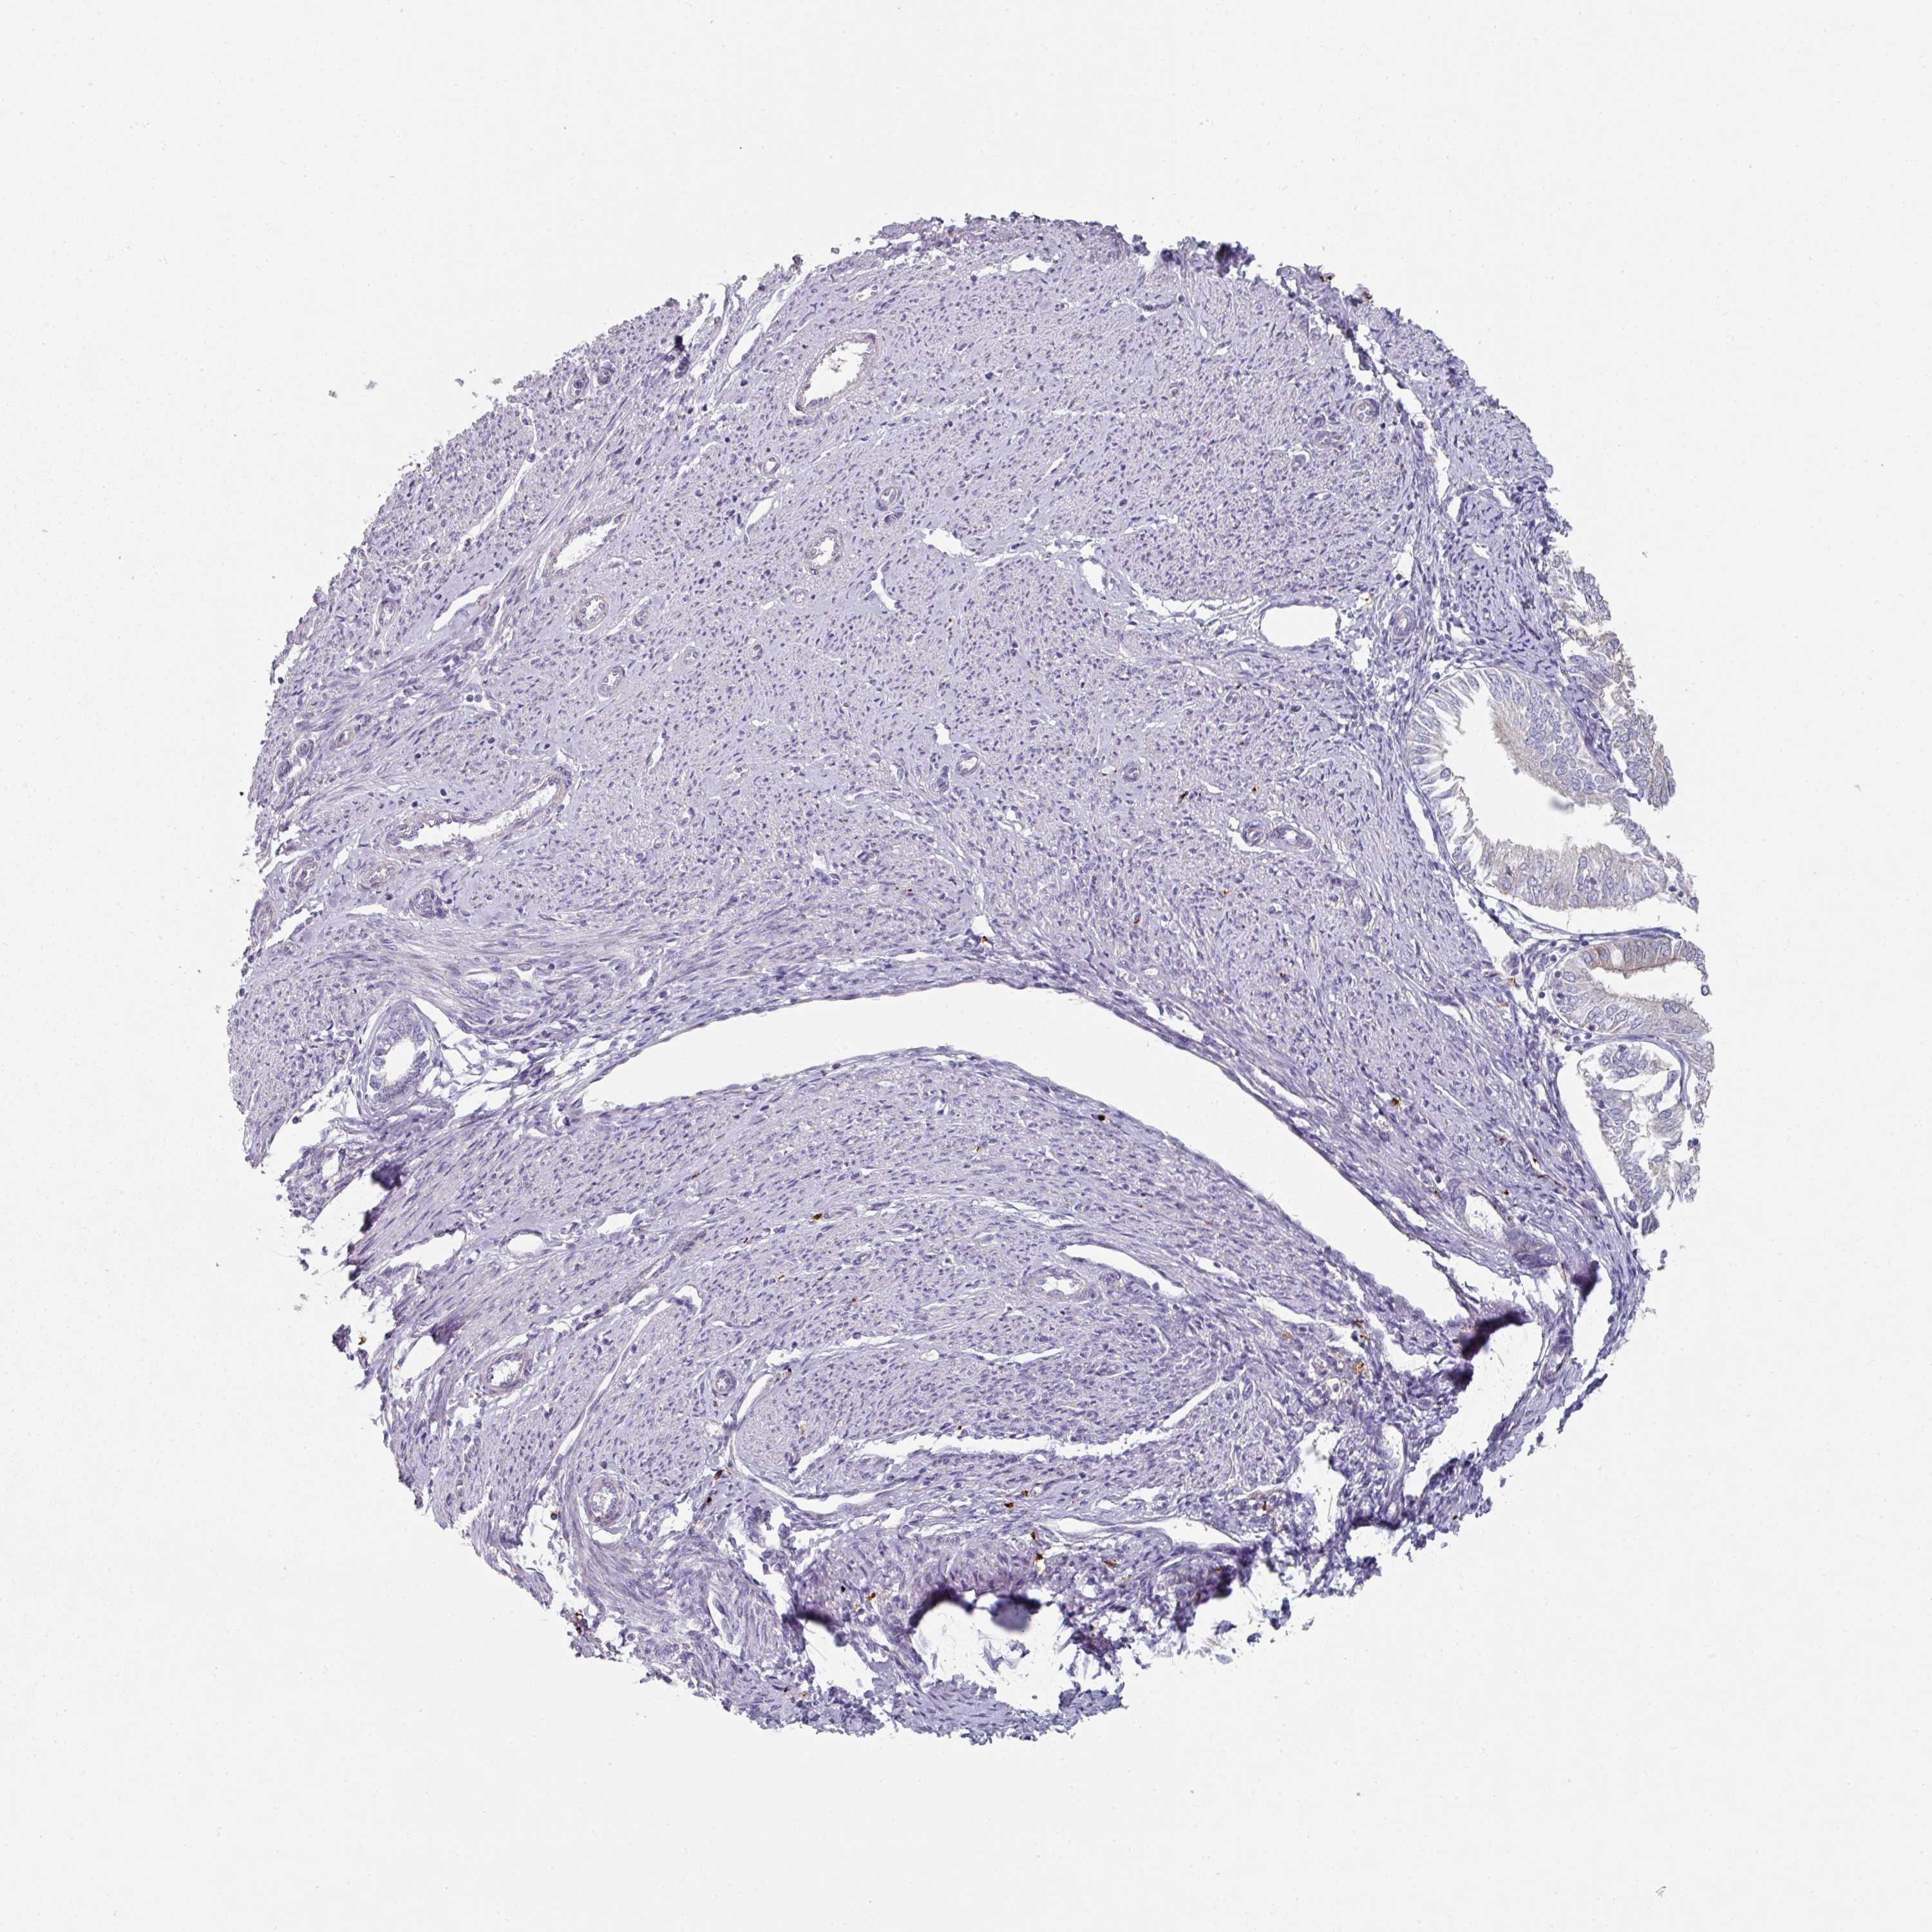

ENDOMETRIAL CANCER - Protein expressioni

A mouse-over function shows sample information and annotation data. Click on an image to view it in a full screen mode. Samples can be filtered based on level of antibody staining by selecting one or several of the following categories: high, medium, low and not detected. The assay and annotation is described here.

Note that samples used for immunohistochemistry by the Human Protein Atlas do not correspond to samples in the TCGA dataset.

Antibody stainingi

Antibody staining in the annotated cell types in the current human tissue is reported as not detected, low, medium, or high, based on conventional immunohistochemistry profiling in selected tissues. This score is based on the combination of the staining intensity and fraction of stained cells.

Each image is clickable and will lead to virtual microscopy that enables deeper exploration of all samples and also displays staining intensity scores, fraction scores and subcellular localization as well as patient and tissue information for each sample.

Antibody HPA052606

Antibody HPA077139

Staining

High

Medium

Low

Not detected

Intensity

Strong

Moderate

Weak

Negative

Quantity

>75%

75%-25%

<25%

None

Location

Nuclear

Cytoplasmic/membranous

Cytoplasmic/membranous,nuclear

Adenocarcinoma, NOS